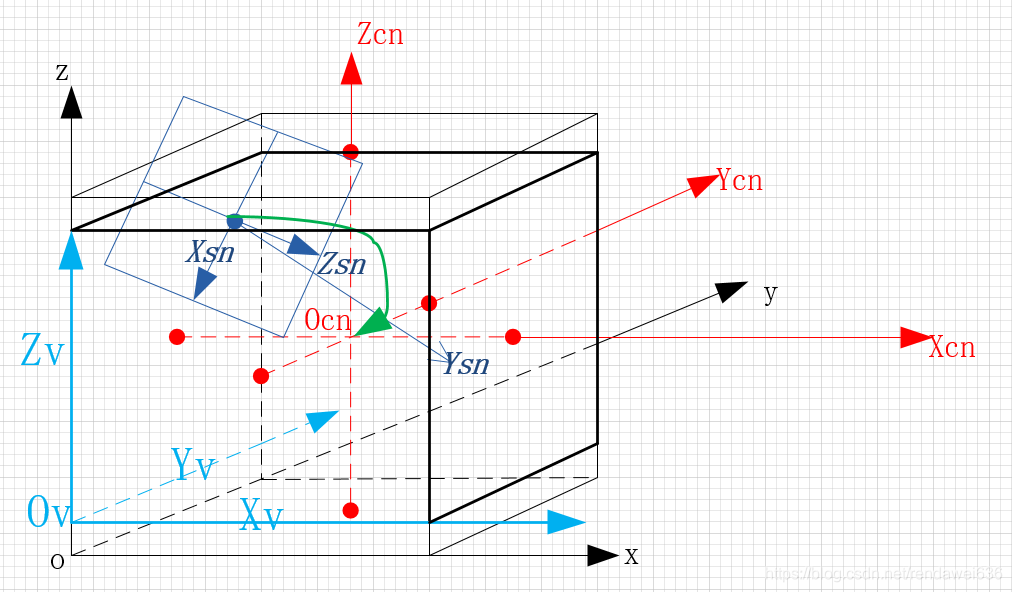

以上的是一个直观的问题描述,在实际渲染算法引擎中,坐标系Osn到坐标Ov之间的变换,是通过一系列的变换的集合,下图就描述了,我们坐标系的定义,其中,比较关键的坐标系是:(坐标系都符合右手螺旋法则)

Ov:原始体素坐标系。坐标方向是Dicom中规定的坐标方向,以图像的左上角为圆心,图像左向右方向是x轴方向,从上到下是y轴方向,z方向是按照右手法则确定,坐标单位是毫米mm。

O:正方体修正坐标系。此坐标系将Ov中最长边作为正方体边长,并且坐标原点和原始Ov的长方体体数据的中心点重合的坐标系。

Ocn:归一化坐标系。归一化是为了后续数值计算方便。将O立方体归一化后,坐标原点和O坐标原点重合。

Osn:内窥镜坐标系。将体素坐标投射到XsnYsn平面上,就是内窥镜的最终的渲染图像。

2 坐标变换

根据上图中的建标方式,可以将坐标的变换分为两步,第一步是,计算Ocn到Osn坐标的变换矩阵,此矩阵可以将Osn中的坐标值转化到Ocn中的坐标值。第二步,Ov到Ocn的变换矩阵,将Ocn中的坐标值转化为Ov坐标值。